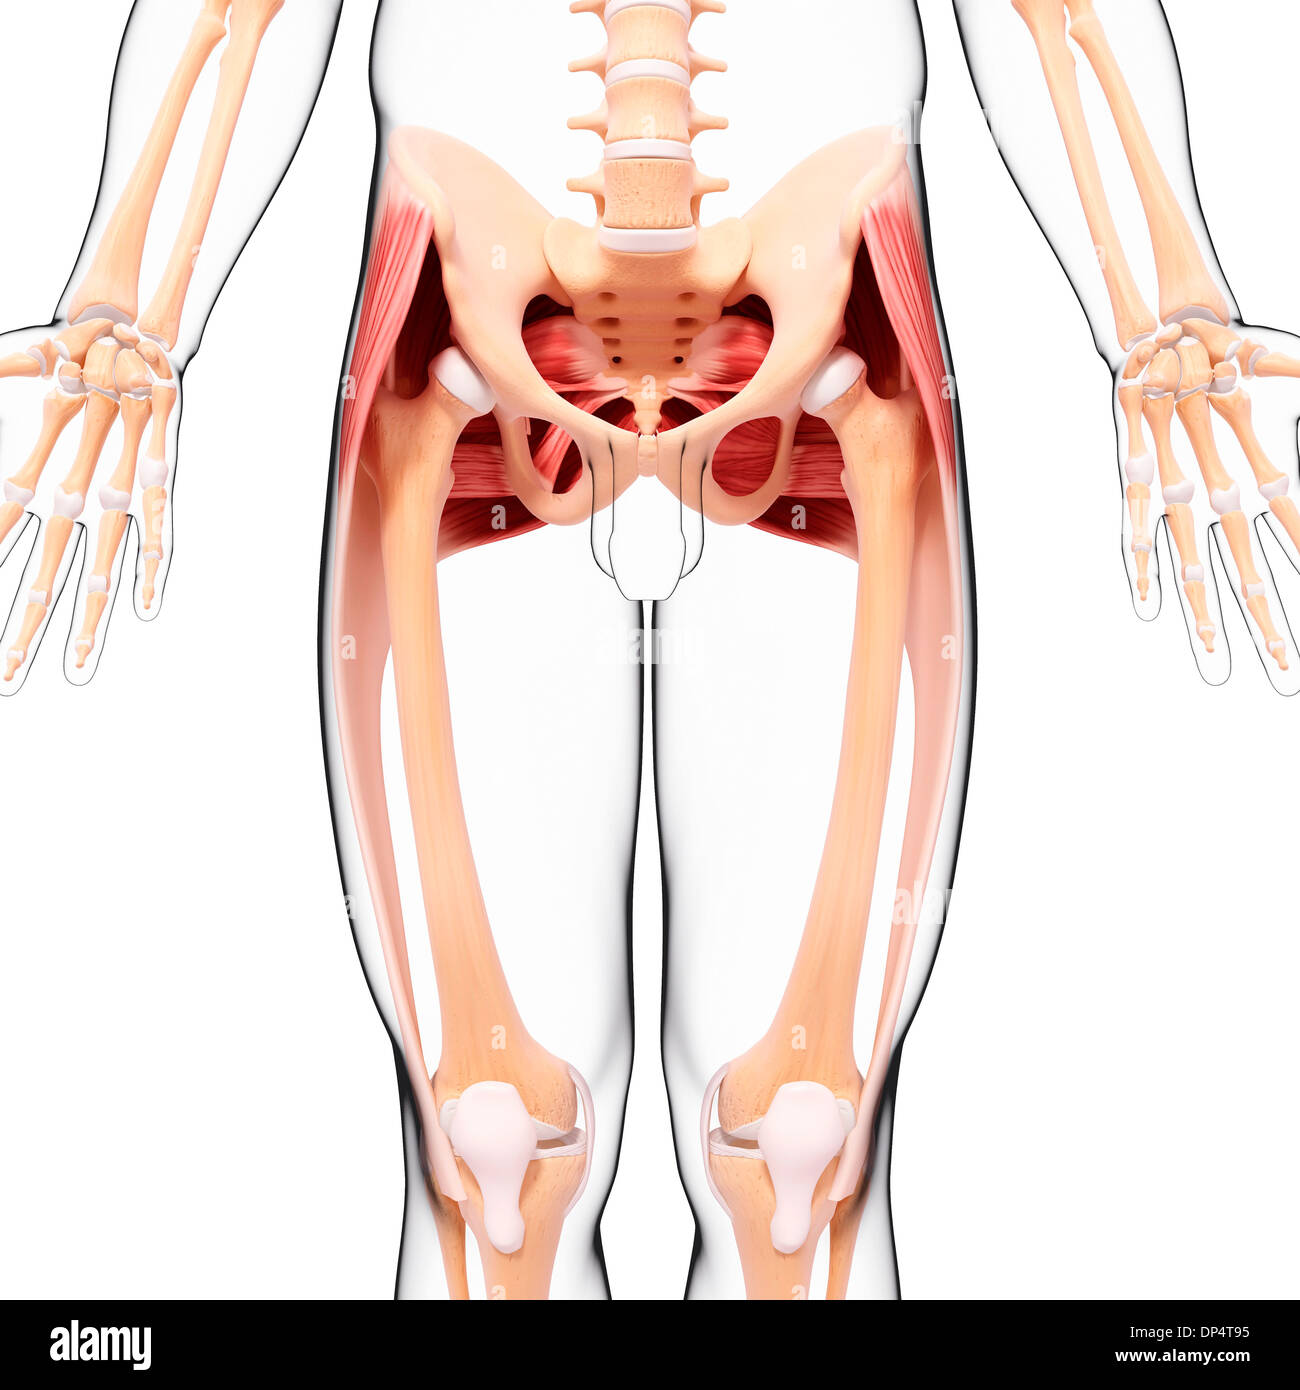

Human Muscular System Leg Muscles Tensor Fasciae Latae Muscles Anatomy Stock Photohttps://www.alamy.com/image-license-details/?v=1https://www.alamy.com/human-muscular-system-leg-muscles-tensor-fasciae-latae-muscles-anatomy-image700771049.html

Human Muscular System Leg Muscles Tensor Fasciae Latae Muscles Anatomy Stock Photohttps://www.alamy.com/image-license-details/?v=1https://www.alamy.com/human-muscular-system-leg-muscles-tensor-fasciae-latae-muscles-anatomy-image700771049.htmlRF3CM2THD–Human Muscular System Leg Muscles Tensor Fasciae Latae Muscles Anatomy